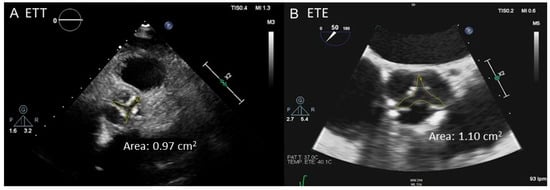

2.2. Transesophageal Echocardiography

- Planimetry. Cine sequences, selecting a perpendicular plane to the AV orifice, can be used to obtain a direct planimetry of the AVA. Such a measurement has been shown to be reproducible and correlates well with the AVA obtained by planimetry with 2D TEE [46] and with AVA estimated by catheterization [47]. Like MDCT, CMR planimetry slightly overestimates AVA compared to TTE [48]. Using Hakki’s formula, which is a simplification of Gorlin formula [49], AVA is mildly underestimated [48,50] compared to catheterization. Despite intra- and interobserver reproducibility of AV planimetry by CMR is excellent [48,50], its application is limited in certain scenarios such as the presence of a non-planar orifice, a highly calcified AV or arrhythmias (i.e., AF) [45].

- Morelli, S.; De Castro, S.; Cartoni, D.; Perrone, C.; Beni, S.; Bernardo, M.L.; Ferrante, L.; Giordano, M. Planar determination of the aortic valve area with transesophageal echocardiography with multiplanar probe in patients with aortic stenosis and insufficiency. Comparison with transthoracic Doppler echocardiography. G. Ital. Cardiol. 1995, 25, 851–857. [Google Scholar]

- Tribouilloy, C.; Shen, W.F.; Peltier, M.; Mirode, A.; Rey, J.-L.; Lesbre, J.-P. Quantitation of aortic valve area in aortic stenosis with multiplane transesophageal echocardiography: Comparison with monoplane transesophageal approach. Am. Heart J. 1994, 128, 526–532. [Google Scholar] [CrossRef]

- Hoffmann, R.; Flachskampf, F.A.; Hanrath, P. Planimetry of orifice area in aortic stenosis using multiplane transesophageal echocardiography. J. Am. Coll. Cardiol. 1993, 22, 529–534. [Google Scholar] [CrossRef] [PubMed]